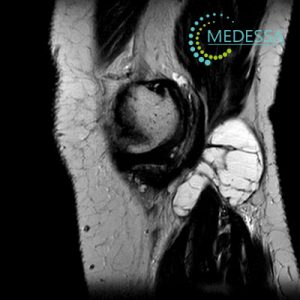

МРТ колінного суглоба – Кіста Бейкера або бурсит Бейкера

Кіста Бейкера, також відома як кіста синовіальної оболонки або бурсит Бекера, є аномалією, пов’язаною з суглобом, найчастіше з колінним суглобом. Ця кіста формується внаслідок накопичення суглобової рідини в задній частині коліна, утворюючи мішок або кісту.

Магнітно-резонансна томографія (МРТ) є потужним інструментом для діагностики різних станів та захворювань, включаючи проблеми з колінним суглобом, такі як кіста Бекера. Ось як МРТ може допомогти у виявленні та лікуванні:

МРТ надає докладні зображення м’яких тканин, кісток та суглобів, що дозволяє лікарям побачити структурні зміни в колінному суглобі, включаючи кісти, пошкодження хряща, запалення та інші аномалії.

МРТ може допомогти у точній локалізації та визначенні розмірів кісти. Це важливо задля розробки ефективного плану лікування.